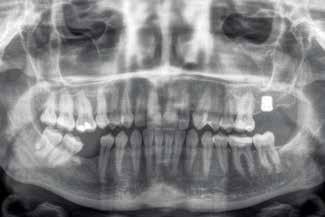

None of the implants failed during the follow-up period, resulting in 100% survival and no adverse surgical or prosthetic events were recorded. Images 1-7 show one of the cases included in the study.

Figure 1. Initial X-ray of the case, where we can see in the second quadrant an edentulous section corresponding to tooth 27 that will be rehabilitated using dental implants.

Figure 3. Post-surgical panoramic X-ray with the recently placed implant.

Figure 2 Figure 3 Figure 4 Figure 1

Figures 5-6 Clinical images of the patient at the time of crown placement. Figure 7. Radiographic image at 4 years of follow-up showing the bone stability of the implant and the rehabilitation.